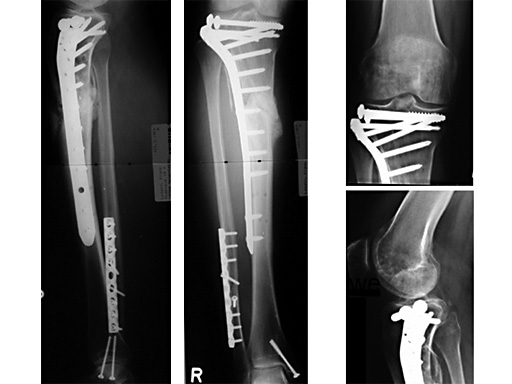

The LIS system for the proximal tibia is an anatomically pre-contoured implant for the treatment of fractures of the proximal tibia. In the course of a prospective clinical study, 135 patients with 138 fractures were treated with the new system at 13 European trauma centers from June 1998 to March 2000 and the cases were documented. The follow-up period was at least 12 months and ended in June 2001. Principle clinical investigator is C. Krettek, Hanover. AOCID monitored the study.

The inclusion criteria took in fractures of all degrees of severity of the proximal tibia and the tibial shaft. The fractures were classified as 110 fractures of the proximal tibia (AO 41) and 28 tibial shaft fractures (AO 42) according to the AO fracture classification system; type C fractures accounted for a total of 66% (n=91). A follow-up rate of 94% was achieved with reference to the number of fractures treated. The results of the study were evaluated immediately in close collaboration with the Principal Clinical Investigator. It is expected that the evaluation will be completed by the end of 2001; the results will be summarized and published in a final report.